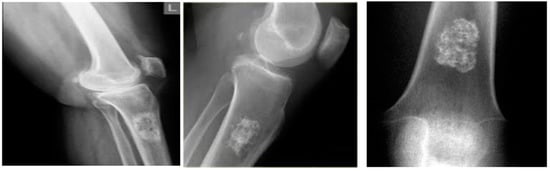

4.2. Results for Pre-Processing